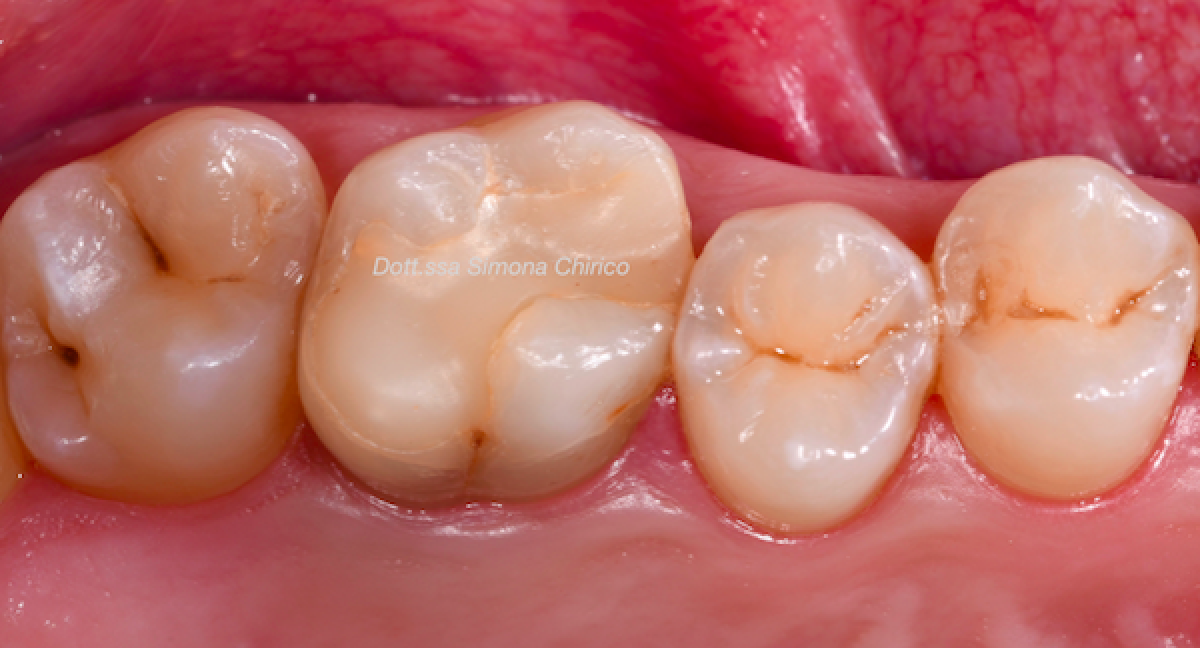

The reconstructed element were checked one week after the last appointment to check for any problems during the function (Fig.9 a-b ).